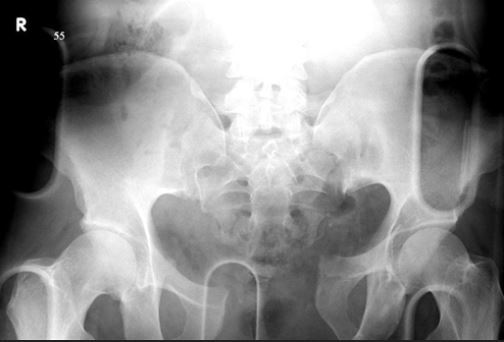

A 34-year-old female presents to the trauma bay with hemodynamic instability following a motor vehicle collision. A chest radiograph shows a left-sided hemothorax and her pelvis radiograph is shown in Figure A. Which of the following is the next most appropriate step in managment?

This is an APC III and requires pelvic binder in resuscitation bay